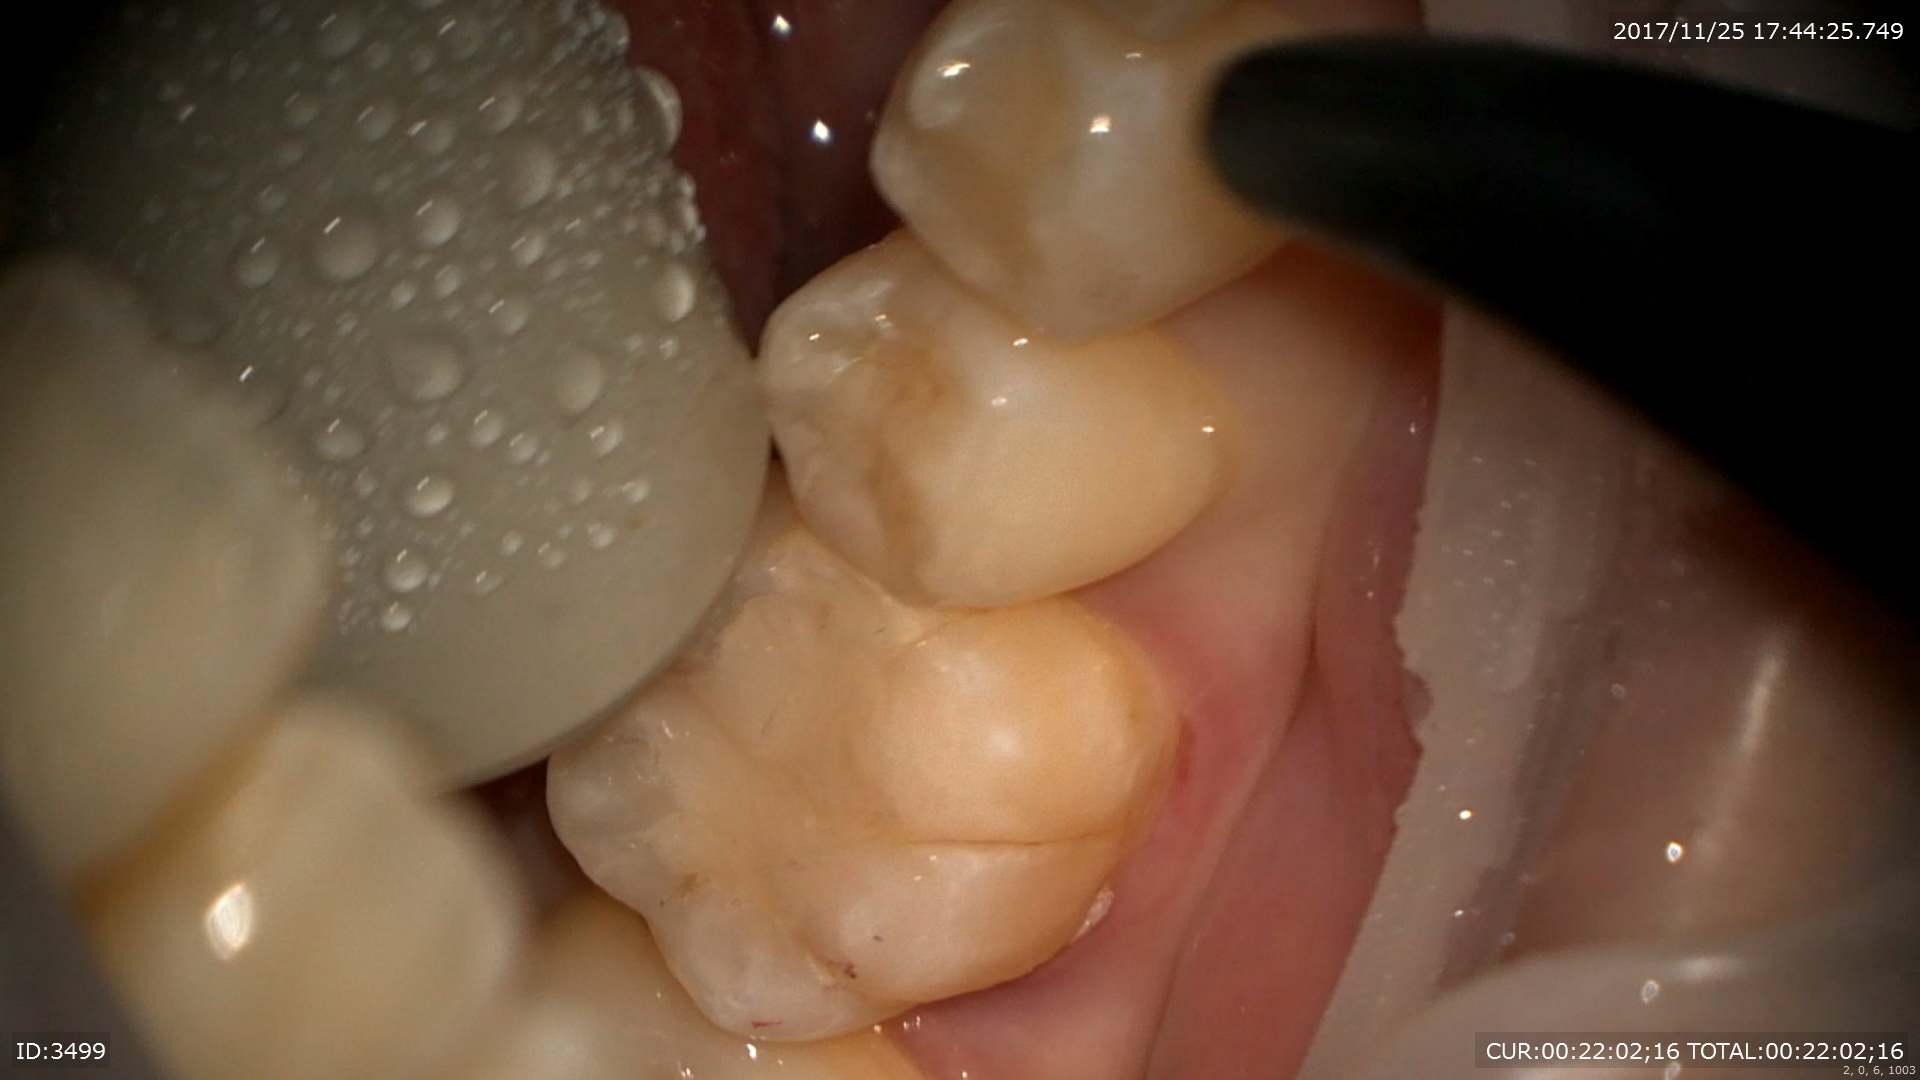

さて今日のマイクロスコープ治療を御紹介。

ケース1:マイクロエンド 主訴:歯茎が腫れた。口内炎?

ブログを見て頂いている方の中にもこのような症状ありませんか?今回のケースを見て頂くとご理解頂けると思いますが放っておいたら大変な事になる重症な病変でした。

いつも通りまず歯科ドックをして原因を調べます。ドックの結果神経が死んでいました。しかし今回わからなかったのは分岐部といって歯の又の部分にも病変がありました。。。

CTとデンタルをみると髄床から何か管か破折線か見えます。なんだろう。これが分岐部病変の原因ではないかと思います。歯科ドックをしたからここまでわかりました。

さて丁寧に根管を探していきます。

ん?歯髄から結石が!!これもマイクロエキスカで丁寧に取ります。

ん?近心根の中に2根(珍しい)1つは分岐部へ。

非常に珍しいケース。近心の根管の中に分岐部があり根管がご覧の様に縦に並んでいました。根管の形態はご覧の様に様々。だから時間と精密さが求められます。

次回症状が良くなっているといいです。